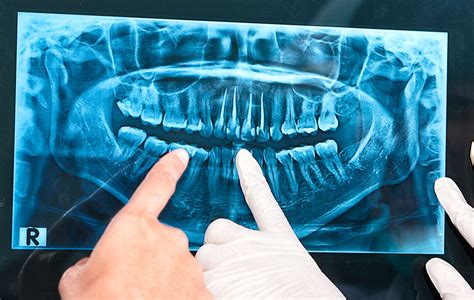

En la práctica odontológica moderna, la radiografía dental se ha convertido en una herramienta indispensable. Estas imágenes permiten a los odontólogos ver lo que a simple vista es imposible detectar, proporcionando una visión detallada de la estructura interna de los dientes, huesos y tejidos circundantes.

Este método de diagnóstico es fundamental en la odontología dado que ayuda a identificar problemas que no son visibles durante un examen clínico regular. Las radiografías dentales son esenciales para detectar caries ocultas, identificar infecciones en las raíces, evaluar la pérdida ósea causada por la enfermedad periodontal, planear tratamientos de ortodoncia y detectar quistes y tumores.

Las radiografías dentales son imágenes obtenidas mediante el uso de rayos X, que permiten a los odontólogos ver las estructuras internas de la boca, como los dientes, huesos maxilares y tejidos circundantes. Al ofrecer una visión detallada de la estructura interna de la boca, permiten diagnósticos precisos y una planificación de tratamientos efectiva, asegurando una atención de alta calidad para los pacientes.

- Radiografías Extraorales: Son técnicas de diagnóstico por imagen en odontología en las que el sensor o película radiográfica se coloca fuera de la boca del paciente. Es fundamental para los análisis cefalométricos que determinan la posición y alineación de los dientes, así como la relación entre los maxilares y el cráneo.